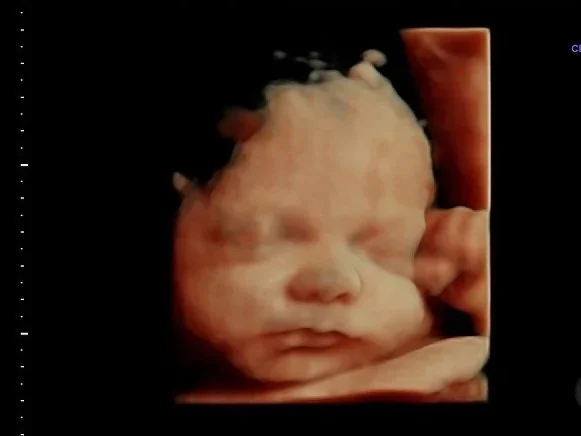

30-minute 3D/4D/HD Ultrasound

Looks best at 28 weeks+ but can be done as early as 15 weeks

During this 30-minute appointment we will attempt to see your baby make faces, see their hands and feet move, and check for hair!

6 Ultrasound sound prints

Baby Position

Hear Heartbeat

$128

Come again and again for $85

To book this use the “returning visit” tab upon booking.